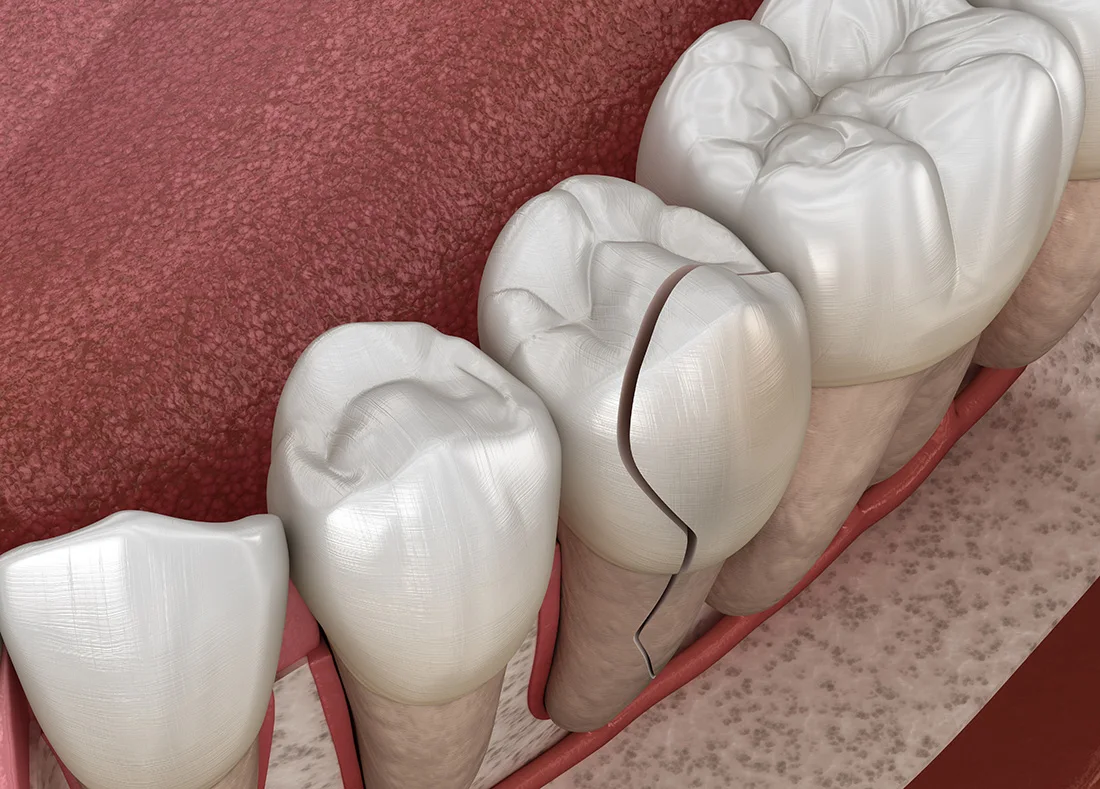

If you chip, break, or crack a tooth, you need professional care to assess the damage and prevent further problems. It's difficult to know how bad the damage is without a full examination. Ignoring it can lead to infections and other issues. Call us immediately for an appointment so we can check the damage, determine how to fix and protect your tooth, and create a plan to get you out of pain.